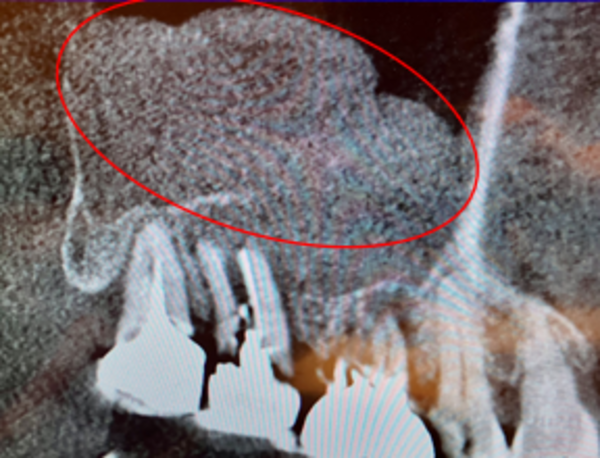

なお、抜歯前に撮影したCT画像では、副鼻腔内膜が歯由来の感染症で炎症を起こし、かなり肥厚しているのが確認されたのですが、サイナスリフト前に再度CTを撮影したところ、肥厚は消失し綺麗になっているのが確認できました。

白っぽく膨らんで見える部分が肥厚です。抜歯後には感染が除去されたことにより肥厚が綺麗になくなっていました。